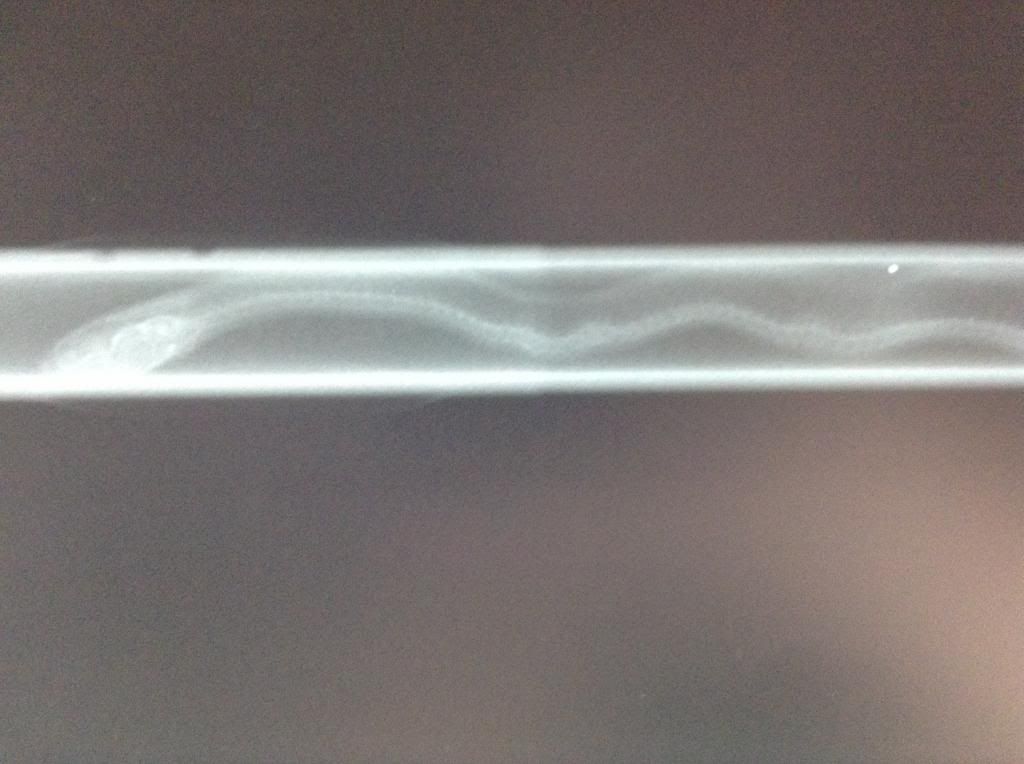

THEN he got stuffed (again, not literally) into a weird tube like device and carried around like a sword (not really) and was thus x-rayed a few different times.

Angry noodle in a tube!!! (he had scrunched himself up and wouldn't move lol)

Neck kink and one a little further down

Just past the neck, midway-ish down the body

A little further still

Even though he was scrunched up in the tube, you can clearly see where the kinks are :( poor little guy...my boss looked at 'em and thought he might (maybe) already be developing arthritis...wouldn't surprise me with kinks like that...

I believe the calcified areas that resemble arthritis are just calcified areas. I don't think I would sweat that too much, based on conversations I've had with my vet about kinked animals. The spine builds up buffers around the kinks, and they don't seem to be painful like arthritis.